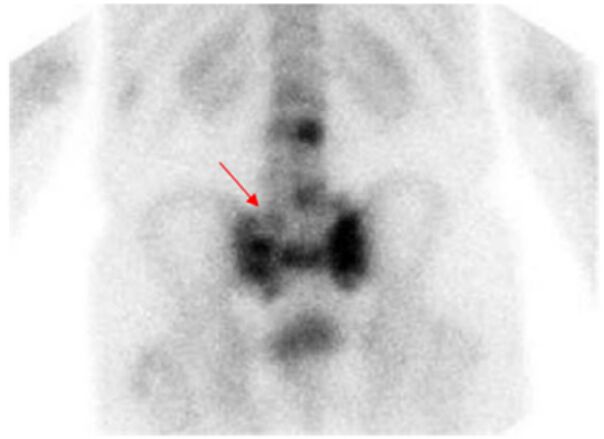

42.二歲女童反覆泌尿道感染,欲安排相關的檢查,下列敘述何者正確?(A)核醫檢查會造成較多輻射暴露,因此不應用於兒科病人 (B)超音波確認有單側水腎,可確認泌尿道感染因膀胱輸尿管逆流(vesicoureteric reflux, VUR)造成,應立刻安排手術處理 (C)可用直接放射性同位素膀胱造影檢查(direct radionuclide cystography),評估膀胱輸尿管逆流 (vesicoureteric reflux, VUR)(D) 99mTc-DTPA 檢查可評估幼兒膀胱輸尿管逆流(vesicoureteric reflux, VUR)併發的腎臟疤痕(renal scarring)